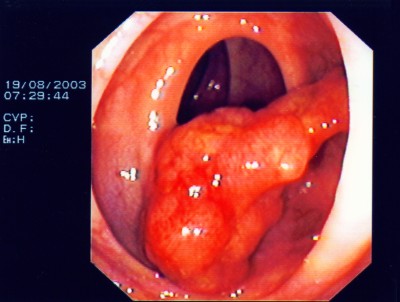

Großer Polyp des Dickdarmes